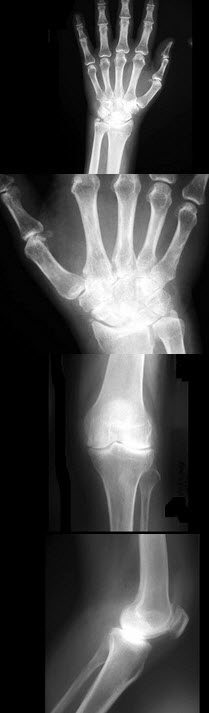

36、单项选择题

女,50岁,手指关节肿痛,晨僵,结合图像,最可能诊断是()

A.关节结核

B.牛皮癣性关节炎

C.痛风性关节炎

D.类风湿关节炎

E.Reiter综合征

76、单项选择题

男,13岁,运动后膝关节疼痛,结合图像,最可能的诊断是()

A.正常影像

B.动脉瘤样骨囊肿

C.骨软骨瘤

D.成骨细胞瘤

E.骨样骨瘤